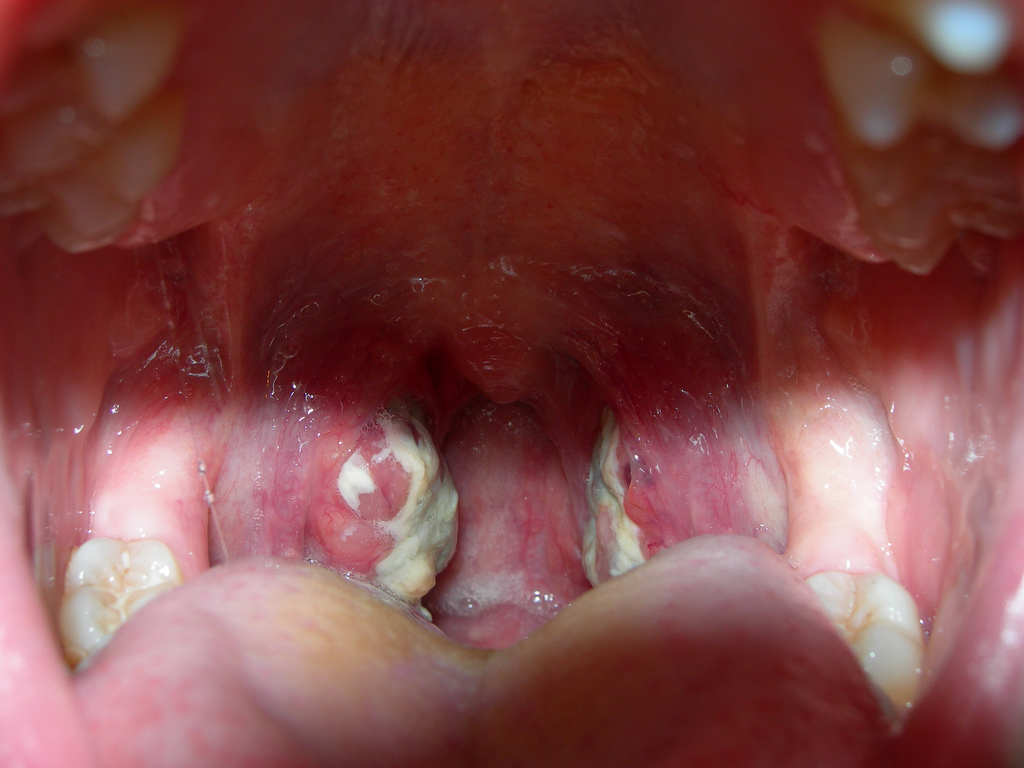

Об остром тонзиллите говорят, когда воспаляются небные миндалины. Стрептококк, проникнув в миндалины, вызывает в них воспалительный процесс, характер которого может быть различным (катаральная, фолликулярная, лакунарная, некротическая ангина).

Если барьерная функция тканей, которые окружают миндалины, снижена, то они тоже вовлекаются в воспалительный процесс, в результате чего возникает паратонзиллит (паратонзиллярный абсцесс – острое воспаление в мягких тканях миндалин).

При осмотре миндалин отмечается их значительное увеличение и наличие желто-белого гнойного налета или беловатых пузырьков (фолликулов).